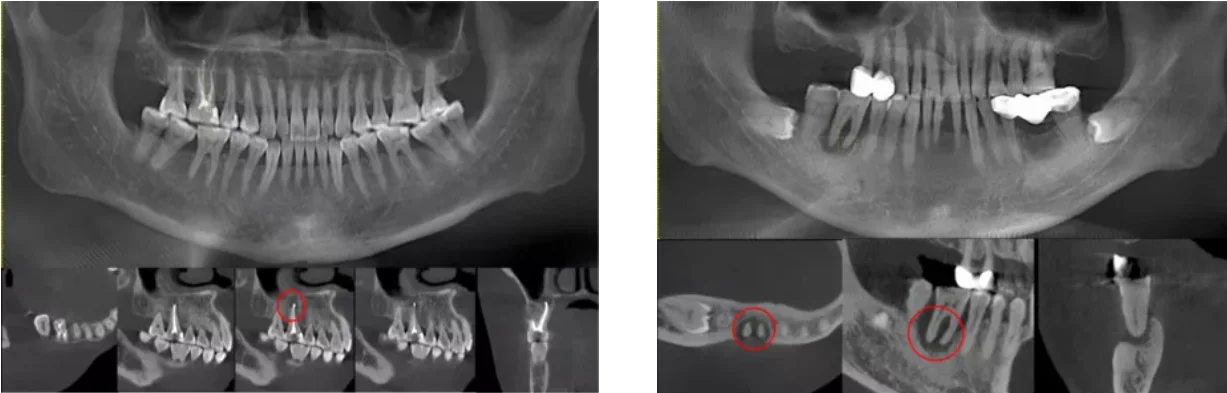

संग्रह 2021: रूट कैनाल एक्स रे निदान

यहां आपको वह मिलेगा जिसकी आपको तलाश थी - रूट कैनाल एक्स रे निदान

These 5 signs says you may need root canal treatment know how this treatment is done in hindi र ट क न ल ट र टम ट क ओर इश र करत ह य 5 स क त ज न क य (फाइल का प्रकार jpg)

These 5 Signs Says You May Need Root Canal Treatment Know How This Treatment Is Done In Hindi र ट क न ल ट र टम ट क ओर इश र करत ह य 5 स क त ज न क य

These 5 signs says you may need root canal treatment know how this treatment is done in hindi र ट क न ल ट र टम ट क ओर इश र करत ह य 5 स क त ज न क य और क स क य ज त ह य इल ज (फाइल का प्रकार jpg)

These 5 Signs Says You May Need Root Canal Treatment Know How This Treatment Is Done In Hindi र ट क न ल ट र टम ट क ओर इश र करत ह य 5 स क त ज न क य और क स क य ज त ह य इल ज